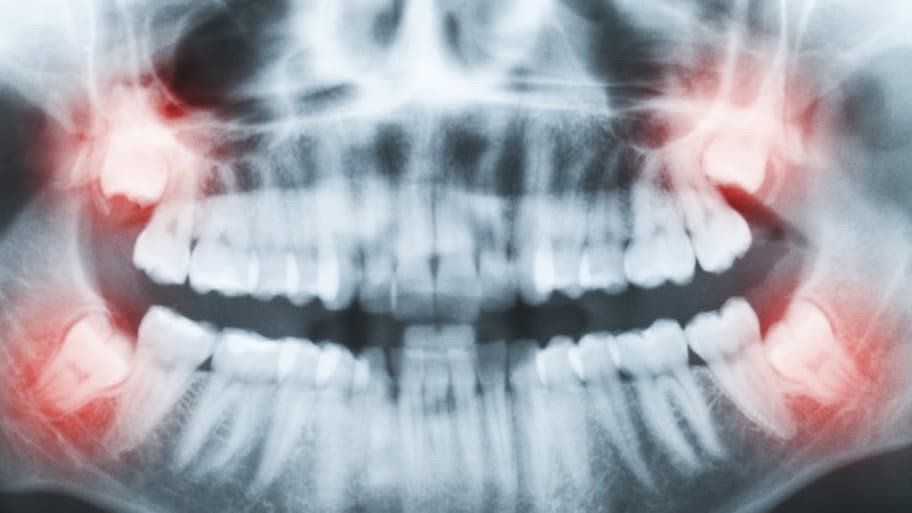

Nhổ răng khôn là tiểu phẫu tương đối phức tạp, tiềm tàng nhiều rủi ro về sức khỏe.

Vào ngày 15/7, một người phụ nữ họ Liao, 42 tuổi, ở bang Kedah, Malaysia, đã đến bệnh viện công để thực hiện tiểu phẫu loại bỏ răng khôn.